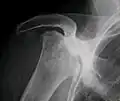

Radiography of total avascular necrosis of right humeral head. Woman of 81 years with diabetes of long evolution. -